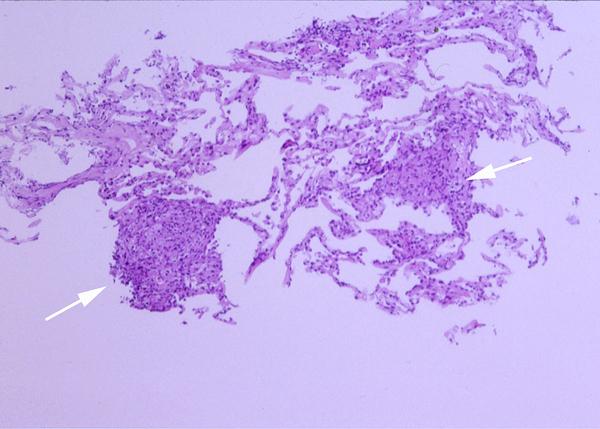

Her clinical and radiologic picture did not improve even after the two canaries were removed from her home. A subsequent bronchoscopy with bronchoalveolar lavage and transbronchial biopsy was done. The lavage revealed 75% lymphocytes and an unrevealing gram stain, GMS and acid fast bacillus (AFB) stain. Two weeks after the bronchoscopy, the lavage grew Mycobacterium avium complex (MAC). The transbronchial biopsy of the right upper lobe is shown in figure 2.

Figure 2: Lung, right upper lobe (H&E, 10 X and 40 X original magnification in Figures 2a and 2b respectively). The transbronchial biopsy of the right upper lobe showed several non-caseating granulomas (white arrows in Figure 2a) with multinucleated giant cells (black arrow in Figure 2b). No acid fast bacilli or fungal organism were identified on AFB and GMS stains respectively.